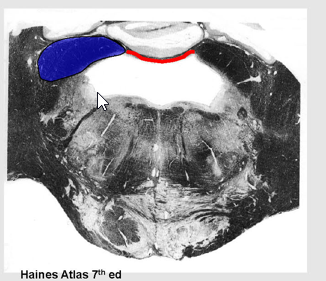

Describe the Inferior/Middle/Superior Cerebellar Peduncles

Locations?

Importance?

inferior cerebellar peduncle (restiform body, ICP)

enter cerebellum in dorsal and lateral position.

Includes:

vestibulocerebellar projections called juxtarestiform body

Middle Cerebellar peduncle:

between the pons and cerebellum

will wrap laterally around the inferior peduncle

superior cerebellar peduncles

in more rostral sections

Forms part of roof of 4th ventricle along with superior medullary velum,

CT membrane between them.